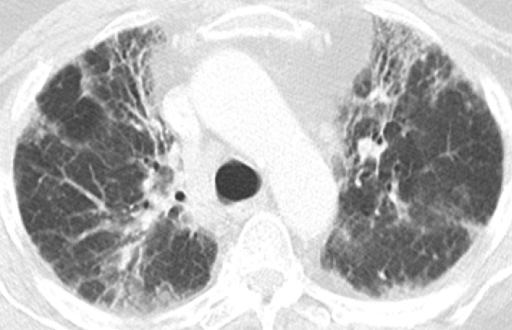

这是另外一个例子,双肺有斑片状的磨玻璃影,同时看到了有少量囊腔,还看到了正常密度的肺脏,双下肺靠近胸膜的地方有少量实变。

ero为什么不显示叶俏教授:HRCT是发现和鉴别「过敏性肺炎」的重要环节,何种表现指向预后不良?使患者发病的危害因素躲在哪些环境中?_https://www.jmylbn.com_新闻资讯_第23张